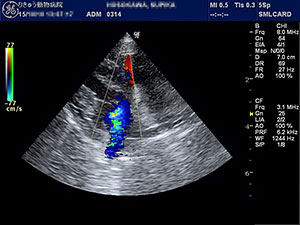

昨今、日本の犬猫たちは益々長寿になってきていますが、それに伴って多くなってきた病気の一つが心臓病です。心臓病にも様々ありますが、フィラリア寄生虫が引き起こす心臓病や栄養欠乏によって生じる心臓病は予防学、栄養学が発展した現在では過去のものとなり、今最もポピュラーな心臓病が「僧房弁閉鎖不全症」です。 僧房弁は心臓の左心房と左心室を仕切る弁です。その僧房弁が、十分に閉じなくなってしまうと、本来ならば一方通行であるはずの心臓内の血液に逆流が生じ、血液がうまく流れなくなってしまうことで、初期には咳、中期以降は肺水腫や失神などの症状を引き起こす疾患です。

この疾患の最も多い原因は、加齢に伴う僧房弁の粘液腫様変性による弁尖の変形、ゆがみ、逸脱などによって、僧房弁の閉鎖が障害されてしまうことです。他には、心室中隔欠損、動脈管開存症、拡張型心筋症などによる左心室の拡大によって、僧帽弁輪が拡大してしまい、うまく閉まらなくなった結果、血液の逆流が生じることもあります。診断は聴診、胸部レントゲン検査、心エコー検査などを使い評価していきます。

心室中隔というのは、左心室と右心室を仕切っている壁です。心室中隔欠損症では、このしきりである心室中隔に、生まれつき欠損孔(穴)が存在してします。そうすると、左心室と右心室の間に血液短絡(バイパス)ができてしまい、通常の血液循環と異なるために、トラブルを生じる心疾患です。犬ではあまり多くはないですが、ミニチュア・ダックスフンド、フレンチ・ブルドックなどの犬種で見られることがあります。猫では、一般的にみられる先天性心疾患です。診断は聴診、胸部レントゲン検査、心エコー検査などで行います。

特に心エコー検査では、心臓の弁の状態や、血流の速さ・向きなどをリアルタイムで見ることができるため、当院では主にこの心エコー検査による心臓の評価に重点をおいています。